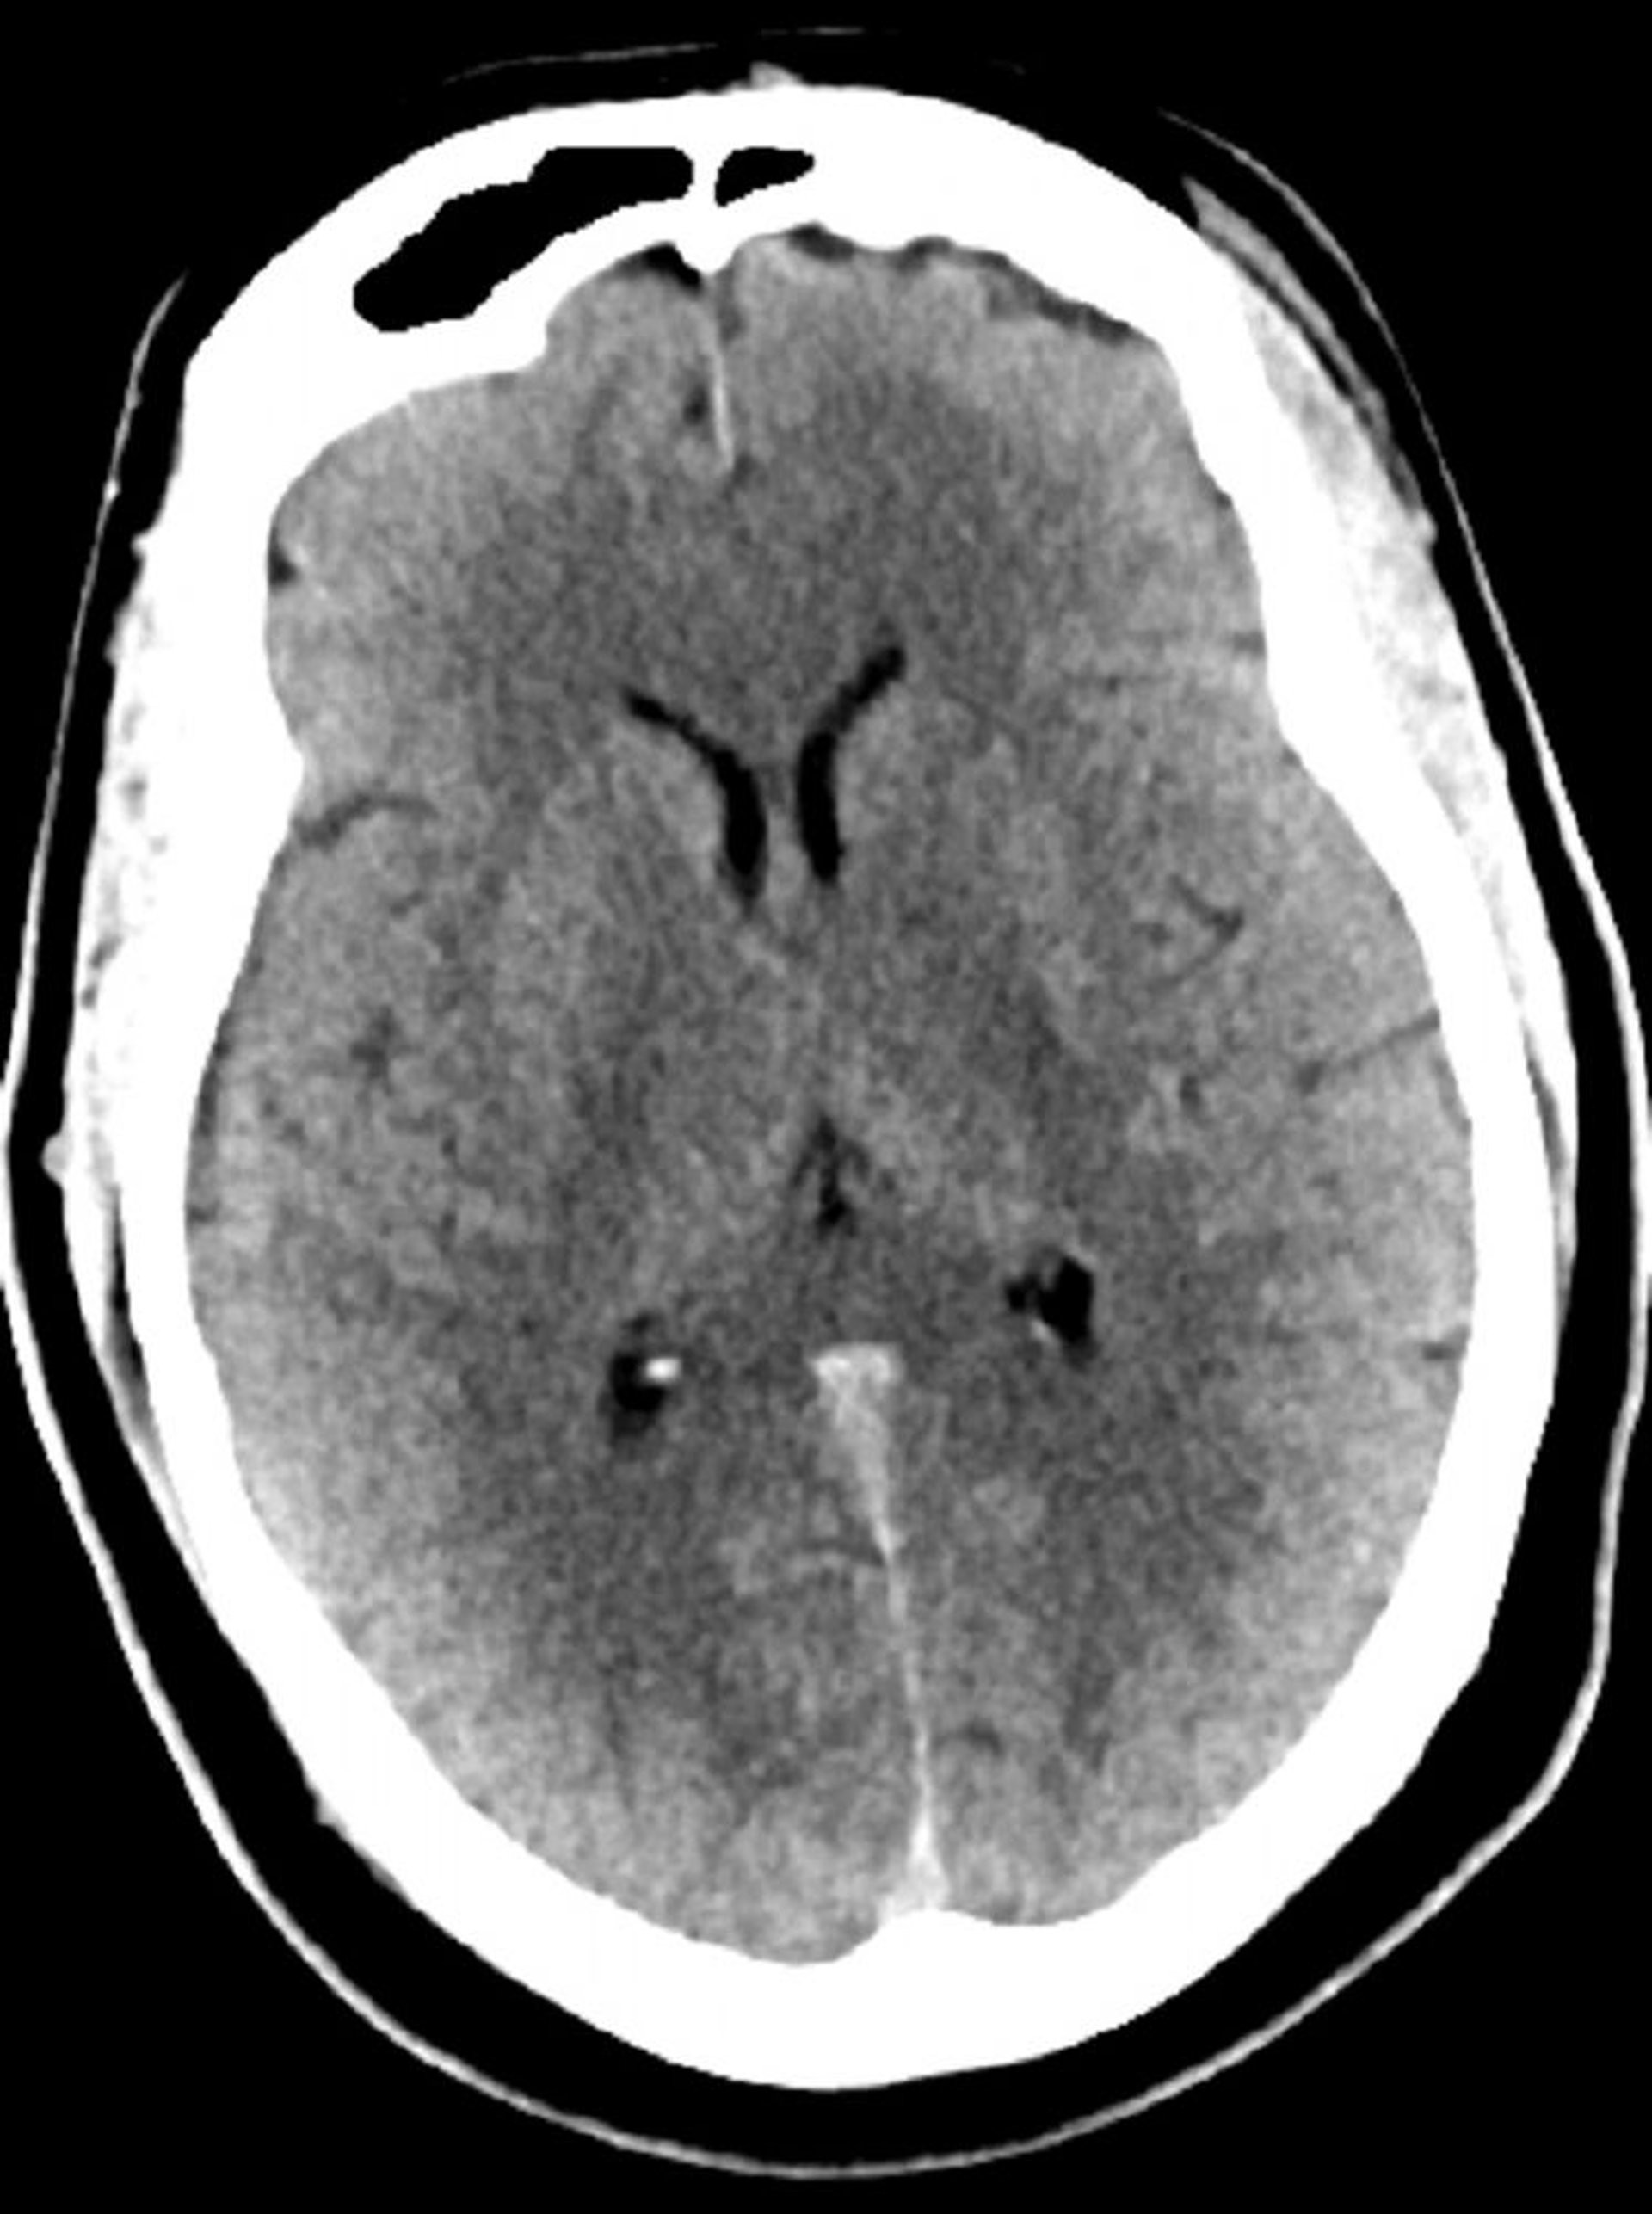

Normaler Kopf CT-Scan (Erwachsene, Alter 30) – Folie 5

Dieses Bild ist ein normaler CT-Scan des Kopfes eines jungen Erwachsenen im Alter von 30 Jahren. Es gibt keine intra- oder extraaxiale Flüssigkeit oder Blutung. Die grauweiße Unterscheidung bleibt erhalten. Ventrikuläre Größe und Sulcalmuster sind normal.